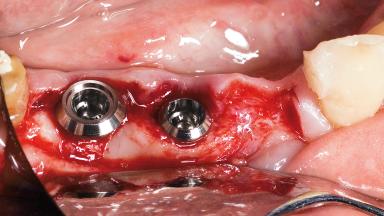

A 55-year-old female patient was referred for consultation and treatment. Her chief complaint was pain associated with the mandibular right second premolar (tooth 45). The patient denied systemic or oral diseases capable of compromising dental care. She had a history of adult periodontitis, for which she continued to be treated. Her response to therapy and motivation towards dental health were considered excellent. Intraoral examination revealed a cantilever fixed dental prosthesis in the mandibular right quadrant, with retainers on teeth 45 and 47,and pontics at sites 44 and 46.The retainer on tooth 45 was loose, and the tooth was carious. Radiographic evaluation confirmed the extent of the caries and the maintenance of bone around tooth 45 and in the pontic region 46.